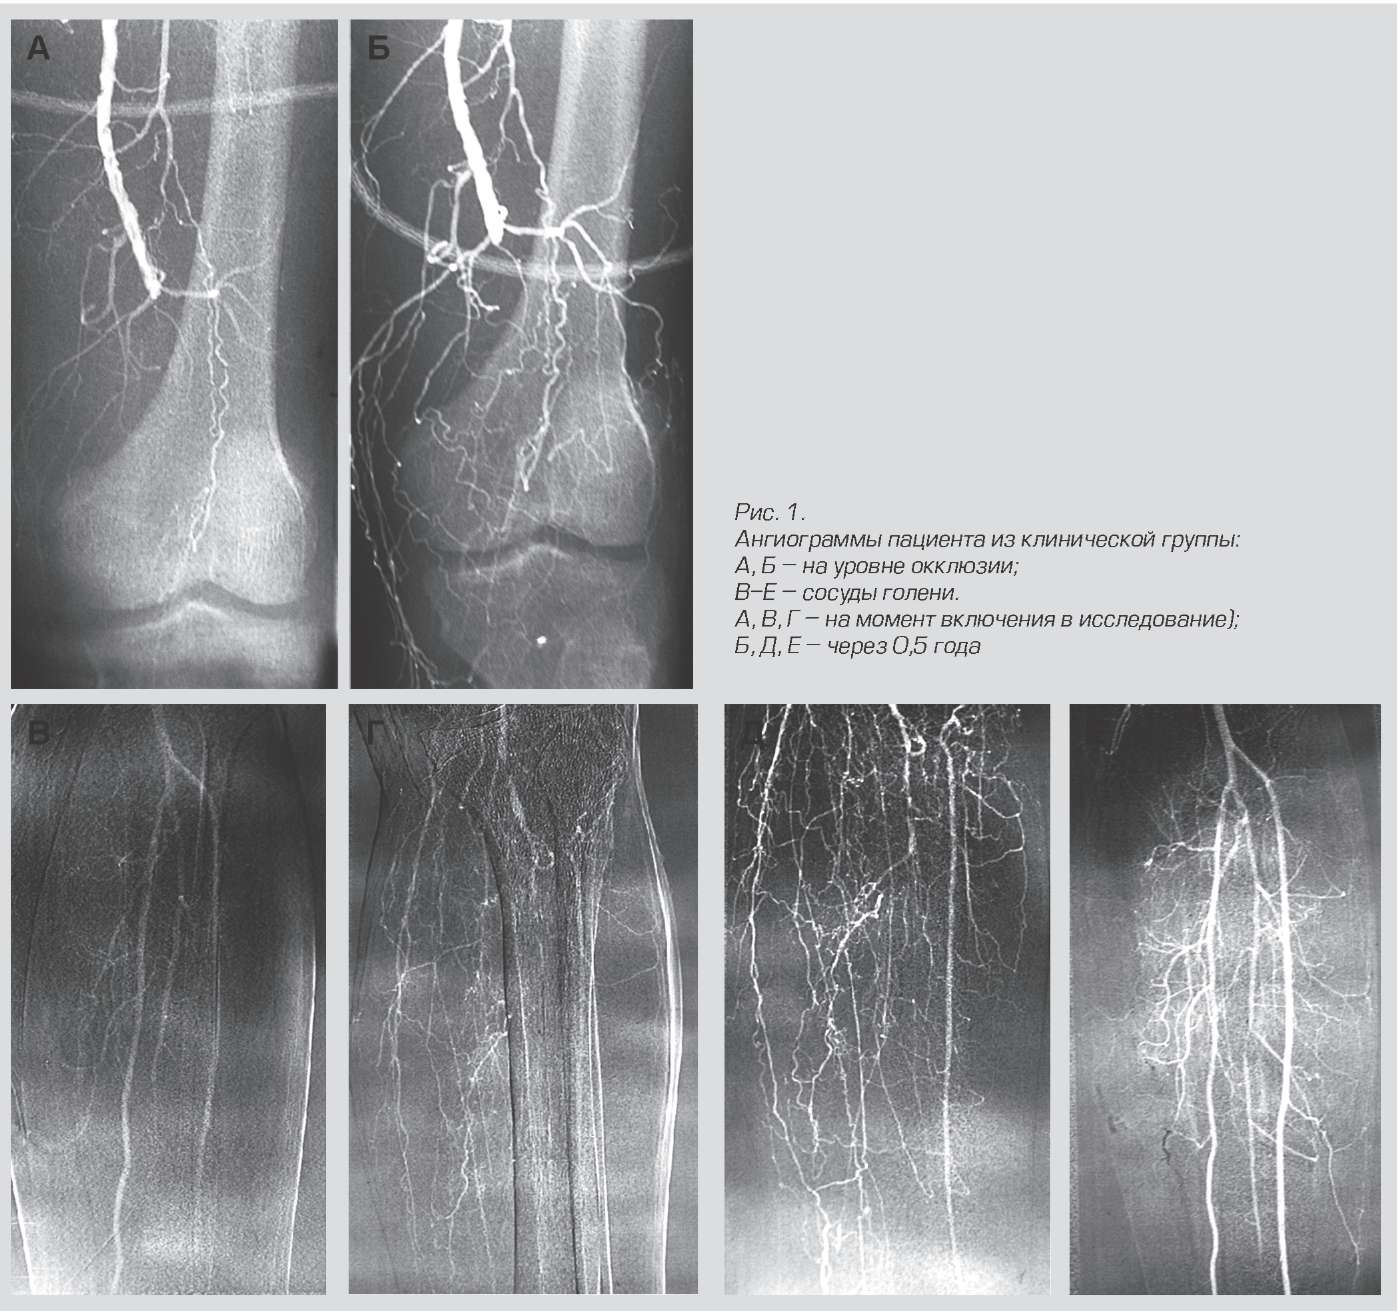

Результаты лечения Неоваскулгеном.

Этот препарат относится к плазмидным, то есть он не редактирует свой геном клетки, а только доставляет в нее плазмиды, которые работают ограниченное время.

Препарат представляет собой кольцевую ДНК (плазмиду), несущую человеческий ген VEGF 165, кодирующий синтез фактора роста эндотелия сосудов (VEGF — Vascular Endothelial Growth Factor). Стимулируя образование и рост коллатеральных сосудов, Неоваскулген призван оказать длительный лечебный эффект и улучшить качество жизни пациентов. Развитие микроциркуляторного русла в ишемизированной ткани нижней конечности способствует насыщению тканей кислородом, заживлению язв, увеличивает дистанцию безболевой ходьбы.

Институт стволовых клеток человека

Механизм действия интересный. Клетки в месте инъекции начинают синтезировать VEGF — это фактор роста сосудов. В результате, в этом участке начинает нарастать новая разветвленная капиллярная сеть. Это критично для пациентов с хронической ишемией нижних конечностей из-за диабета и атеросклероза, например. До этого препарата ампутаций было больше. Сейчас его протестировали еще и для использования в стоматологии для приживления имплантов. Генопрепарат смешивают с костным материалом и ушивают. В итоге сосуды быстро прорастают и формируется нужная ткань без отторжения. На кроликах уже точно моделировали при трансплантации фрагментов черепа. Люди на очереди, насколько мне известно.